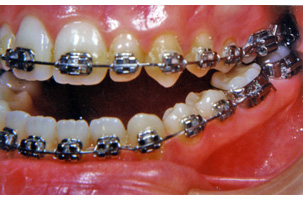

1. Προχειρουργική ορθοδοντική:

Ο ορθοδοντικός καλείται να φέρει τα δόντια της κάθε γνάθου σε θέσεις τέτοιες ώστε μετά το χειρουργείο που θα ακολουθήσει, να επιτευχτεί μια ισορροπημένη σύγκλειση. Η διάρκεια της προχειρουργικής ορθοδοντικής θεραπείας είναι δυνατόν να ποικίλλει κατά περίπτωση από 12 έως 24 μήνες.